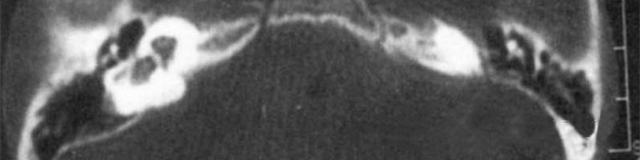

主要根據(jù)聽力學(xué)表現(xiàn)和影像學(xué)檢查。通過(guò)高分辨CT可看到耳蝸畸形。內(nèi)耳MRI顯示膜迷路內(nèi)水充盈,耳蝸扁平,耳蝸第二圈與頂圈間隔缺損,以及半規(guī)管、前庭的畸形。

先天性耳蝸畸形伴前庭和外半規(guī)管發(fā)育不良